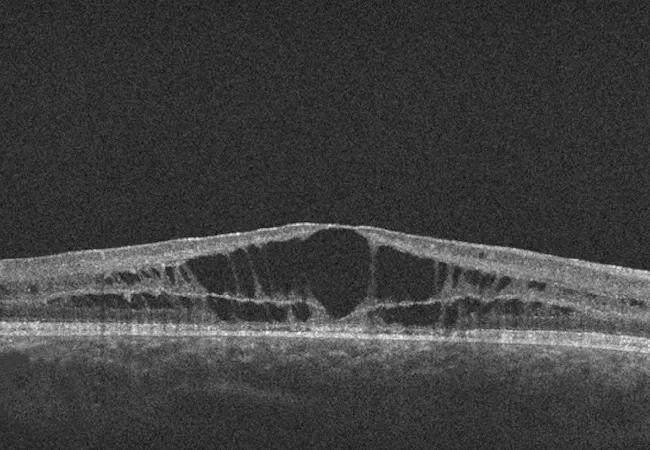

A. Right fundus photograph of a patient with X-linked juvenile retinoschisis. Note the spokelike pattern of cystic schisis cavities in the foveal region. B. OCT demonstrating schisis cavities in the macula of a patient with X-linked juvenile retinoschisis.

Patients with retinoschisis (splitting of retinal layers) typically present in childhood with cystic macular lesions and decreased visual acuity. Most people with the disease record low visual acuity (20/70 to 20/200) by early adulthood (median age 25).

The retrospective interventional study, recently published in Retina, involved 18 eyes in 10 male patients with genetically confirmed XLRS and the presence of cystic macular lesions on optical coherence tomography (OCT). (Two eyes were excluded from the study due to retinal detachment.)